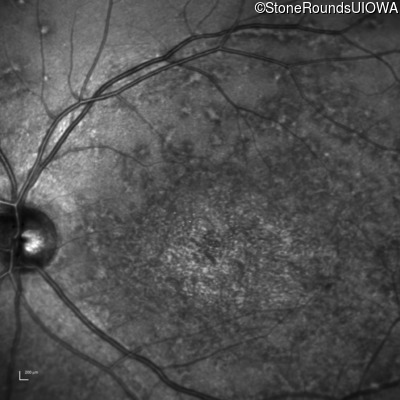

AR Stargardt Disease (IIA)

Age at visit: 42 years

AR Stargardt Disease ABCA4 Val256Val GTG>GTT Gly1961Glu GGA>GAA AR